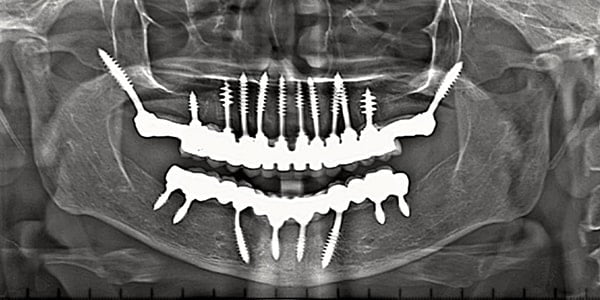

- Slender micro-tapering body & Excellent bending capacity.

Progressive single spiral threads. Higher Bone Implant contact. Improved primary stability. More Resistance to Tensile & Compressive forces. Flame shape threading pattern enables higher primary stability.

Optimum basal bone engagement